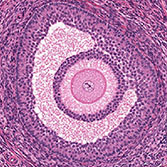

Histology is the study of the microanatomy of cells, tissues, and organs as seen through a microscope. It examines the correlation between structure and function.

Histology Guide teaches the visual art of recognizing the structure of cells and tissues and understanding how this is determined by their function. Rather than reproducing information found in a histology textbook, a user is shown how to apply this knowledge to interpret cells and tissues as viewed through a microscope.

An Aperio slide scanner was used to obtain a high-resolution image of each slide in its entirety. Large tissues are up to 34 GB for a single, uncompressed image of 150,000 x 75,000 pixels.

The contrast, color, and sharpness of each image were adjusted to at least maintain the appearance of the tissue as seen through a microscope. In many cases, these adjustments improved upon their visual appearance.

Unlike low-resolution images, users can interactively explore these large images by zooming-and-panning in real-time. A software-based virtual microscope (Zoomify HTML5 Enterprise) allows the examination of large and small structures in the same specimen.